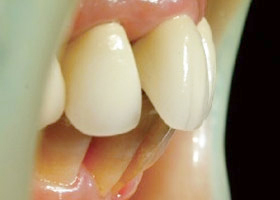

3. 矯正前,明顯可見暴牙。

4. 使用活動式矯正裝置矯正中(矯正方式因人而異)。